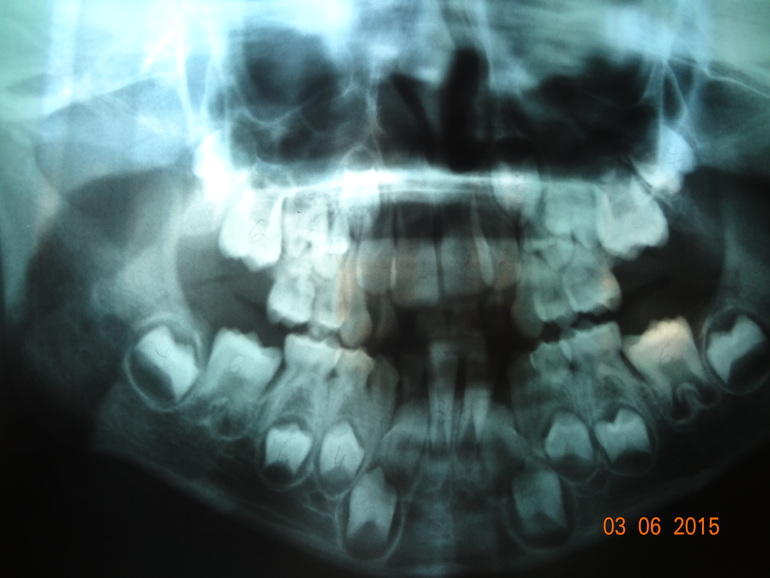

Добрый день Алина! У меня к Вам такой вопрос. Моему сыну 7 лет, месяцев 3-4 назад у него выпали две передние нижние зубы ( то есть 1 и 2 зуб справа на рисунке), но появился только один зуб, а для второго то ли места нет, но его все еще нет. Мы обратились к стоматологу-ортодонту, нам сделали ОПТГ и врач сказала, что срочно нужны ортодонические пластинки (активатор Андрезена-Гойпля) для расширения челюсти, чтобы смогли вылезти все зубы, по ее словам у мальчика зубы вылезут кривыми, так как у него челюсть узкая. Так ли плохи наши дела, или нас разводят просто на деньги. И примерно сколько надо будет носить эти пластинки, я представляю как это будет очень неудобно для ребенка. Может потом когда вылезут все зубы проще будет одевать брикеты для их выравнивания? Спасибо большое.